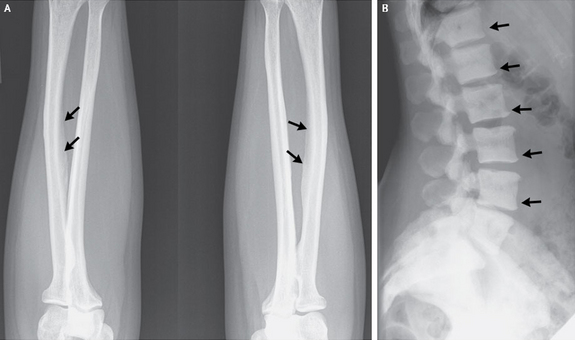

It's not just in India that we see these problems. A 47-year-old U.S. woman developed a bone disease rarely seen in the U.S. after consuming an excessive amount of tea. An x-ray showed calcifications on ligaments (left) and areas of dense bone on the spinal vertebrae (right). Credit: New England Journal of Medicine ©2013.